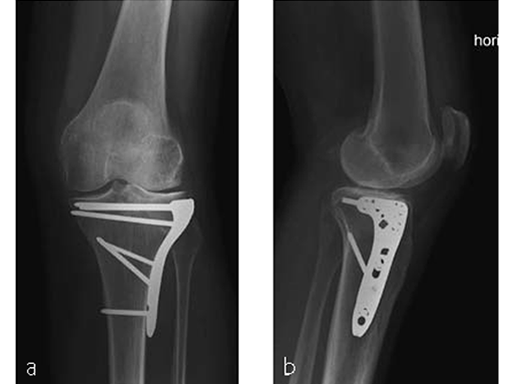

The area was functional soon after treatment (Fig 3), and the patient was able to experience weight bearing of 20 kg for the first 6 weeks. She was completely pain free after 6 weeks (Fig 4) with excellent muscular function and coordination, therefore unlimited weight bearing after the first follow-up was enabled.